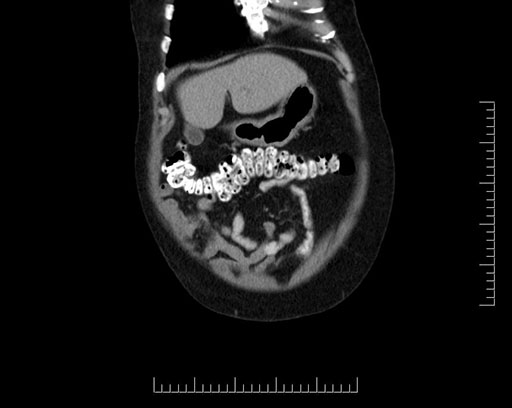

Coronal - stented